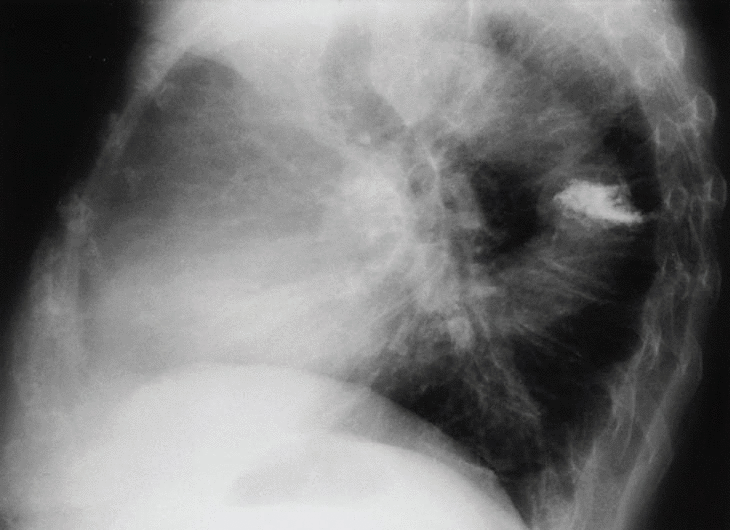

En la radiografía posteroanterior y lateral de tórax observamos como hallazgo más significativo una disminución de la altura y aumento de densidad de un cuerpo vertebral dorsal medio.

Fig. 2.

En esta paciente, coincidiendo con el dolor, se realiza radiografía dorsal donde se aprecia aplastamiento D5-D8. Posteriormente en la resonancia magnética se demuestra fractura y aplastamiento reciente de D7 en probable relación con la osteoporosis que presenta. Se le realizó una vertebroplastia mejorando clínicamente en el plazo de varios días.